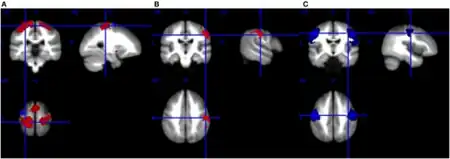

{{cite book}}: CS1 maint: location (link) - ↑ "Patient with amyotrophic lateral sclerosis (ALS) (case | Open-i". openi.nlm.nih.gov. Archived from the original on 15 December 2018. Retrieved 12 December 2018.